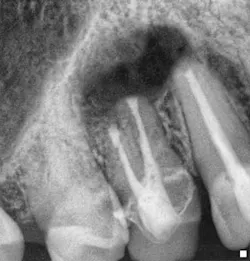

Fig. 11: Surgical postop radiograph.Surgical endodontic treatment was performed and the site of the periapical pathology debrided. No internal or external root fractures were detected, and a surgical seal was prepared at the apex of tooth No. 10 using MTA after ultrasonic preparation to ensure there was no potential for further recontamination of the apical tissues. A bone graft and resorbable membrane were placed to maximize the prognosis for osseous and soft tissue healing. The six-month recall radiographs show graft stability radiographically. There has been no recurrence of the buccal sinus tract, the periodontal attachment is intact, and the patient remains symptom-free. Case 3 Endodontic treatment was performed due to the development of buccal swelling and nonvitality on testing by an endodontic colleague. The sinus tract and buccal swelling persisted despite the ideal radiographic technical status of the treatment performed. Surgical treatment was indicated to manage the nonresolution of the presenting pathology.